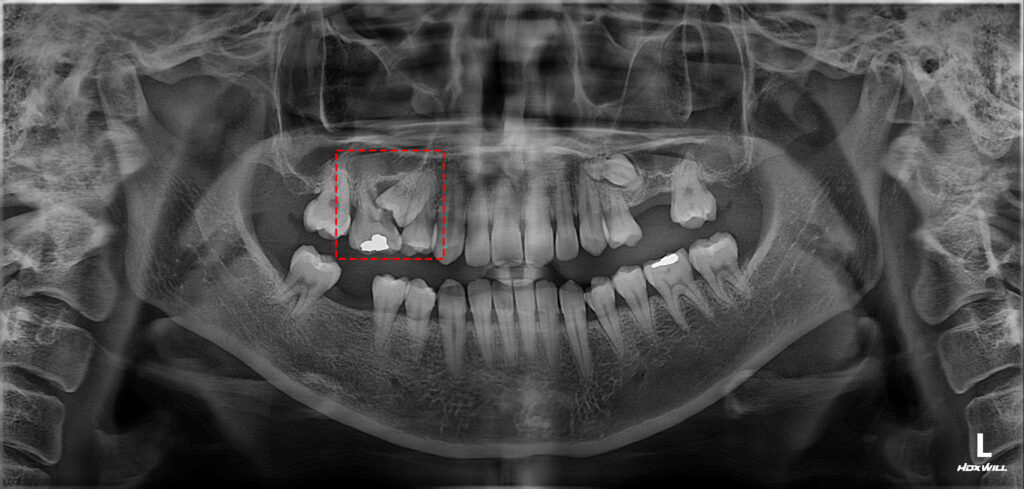

파노라마 사진을 촬영해 보니,

인접면으로 충치가 생겨

치아 뿌리 쪽까지

이어진 상태였는데요.

이 정도로 진행된 충치는

단순한 재치료로는

예후를 기대하기 어렵기 때문에,

장기적인 구강 건강을 위해

발치를 고려할 수밖에 없는

상황이었답니다.